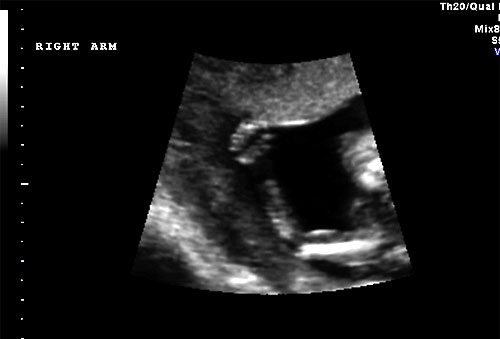

Normal 16 weeks right arm |